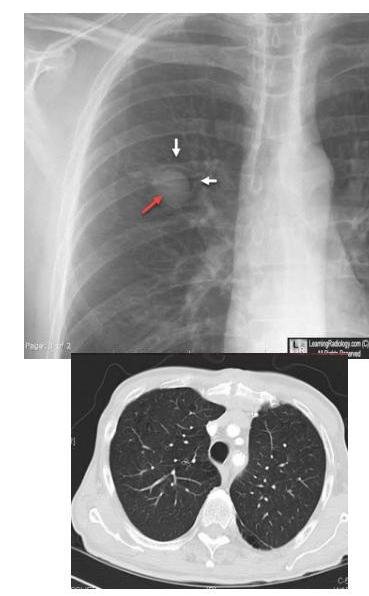

# ASPERGILOSIS ## DEFINICIÓN La Aspergilosis Invasora es la enfermedad causada por diferentes especies del **HONGO** género *Aspergillus*, a partir de un sitio de inoculación e **infección primaria**. El proceso de enfermedad incluye **angioinvasión**, **trombosis** y **tromboembolismo**; esto último, favorece la **diseminación** a otros órganos. La enfermedad invasora por *Aspergillus* afecta principalmente a pacientes **inmunocomprometidos** tales como: con **leucemia**, **linfoma**, **neutropenia prolongada**, **trasplantados** especialmente de **MO** y **pulmón**, aquellos tratados con **inmunomoduladores**, **inmunodeficiencias primarias**, con **enfermedad injerto contra huésped**, **anemia aplásica** y con terapia crónica con **corticosteroides sistémicos**. La forma invasora **incluye** las **infecciones** de las vías **respiratorias inferiores**, **senos paranasales** y **piel** como sitio de entrada. La **diseminación hematógena** o por contigüidad puede condicionar infección a nivel del **sistema nervioso central (SNC)**, cardiovascular y a otros órganos y sistemas. ## EPIDEMIOLOGÍA ## Aspergilosis Invasora: Típica aparición en **Leucemia Mieloide Aguda** y **Trasplantados**. - **Inmunocompromiso** - Mediana de edad 9-11 años (coincide con el pico de **incidencia de leucemias**) - **Neoplasias hematológicas** - **Neutropenia** < 100 cl/mm³ La presencia de **CAVITACIONES PULMONARES PREEXISTENTES** secundarias a infecciones por **Tuberculosis** facilita el desarrollo de Aspergilosis. ## Aspergilosis Broncopulmonar alérgica: - **Hipersensibilidad** asociada a **asma** - **Fibrosis quística** # CLÍNICA Es **inespecífica** en todas sus variables, por lo que es recomendable establecer la certeza diagnóstica con base en los **factores del hospedero** y sus **manifestaciones**. ## RIESGO INTERMEDIO Y ALTO - **Fiebre** y **dolor facial** - Las **lesiones isquémicas** y **úlceras** traducen un **diagnóstico tardío** Otras presentaciones: **Absceso cerebral**, **vasculitis**, **meningoencefalitis**. ## INFECCIÓN DISEMINADA ## ASPERGILOSIS CEREBRAL **Imágenes en anillo**. La aspergilosis **cerebral aislada** puede ocurrir en pacientes **inmunocompetentes**. **Signos neurológicos focales**, **alteraciones en el estado mental** y **cefalea**.  ## Enfermedad cutánea **Diseminación hematógena** o **infección local** (**inserción de catéteres**). **Quemaduras** y **heridas quirúrgicas**. **Eritema** de rápido crecimiento, con **centro necrótico**, frecuentemente **ulcerado**.  ## Aspergiloma * Una **esfera fúngica** coloniza **cavidad pulmonar preexistente** (**habitualmente una caverna tuberculosa residual**). * Se visualiza como **estructura redondeada** dentro de **cavidad pulmonar**, cambia de posición con los movimientos. * **Tuberculosis** 21 %, **no micobacterias** 20 %. ## Osteomielitis **Poco común**. **Extensión local** de **proceso pulmonar**, **sinusal**, **cerebral**. 1.ª en **enfermedad granulomatosa crónica** y **usuarios de drogas**.  # DIAGNÓSTICO ## GOLD STANDARD: CULTIVO / HISTOPATOLOGÍA / PCR / GALACTOMANANO ## CULTIVO Se debe identificar el nivel de la especie para la **susceptibilidad** de los **antimicóticos** disponibles **in vitro**. **Diagnóstico definitivo**. ## HISTOPATOLÓGICO Examen con **tinciones especiales**: PAS y/o Grocott Gomori. **Diagnóstico Definitivo**. ## GALACTOMANANO **Componente** de la **pared fúngica** excretado en la fase de **crecimiento del hongo**, siendo su nivel **proporcional a la carga fúngica** en el tejido. **Positivo en fusariosis**. **Diagnóstico Definitivo**. * Se mide en **suero** y en **lavado broncoalveolar**. * Puede haber **falsos positivos** con el uso de **pipetazo** y otros **betalactámicos**. ## RADIOGRAFÍA DE TÓRAX Se observan **cavitaciones** o **infiltrados**.  (c) Copyright 2021-2022 Joyas ENARM - Todos los derechos reservados - # TOMOGRAFÍA DE TÓRAX Debe realizarse de manera **inicial**, seguida de una **TAC de Alta Resolución** (**cortes finos de 1 mm**) si en la primera se identifica **anormalidad**. **SIGNO DEL HALO**: área de **opacidad en vidrio deslustrado** alrededor de un **nódulo** o **consolidación focal**. Se observa durante la **neutropenia** y es muy **característica** de la **infección invasora por hongos del pulmón**. **Presente** en el **60% de los casos** por 5-7 días posteriores a la **neutropenia grave**. ## TRATAMIENTO  ## **1.ª elección: VORICONAZOL** **Alternativas**: **Isavuconazol** **Efectos secundarios**: **alteraciones visuales**, **hepatotoxicidad** y **fotosensibilidad**. **FORMA INVASIVA**: **Anidulafungina**, **Caspofungina**, **Micafungina**.